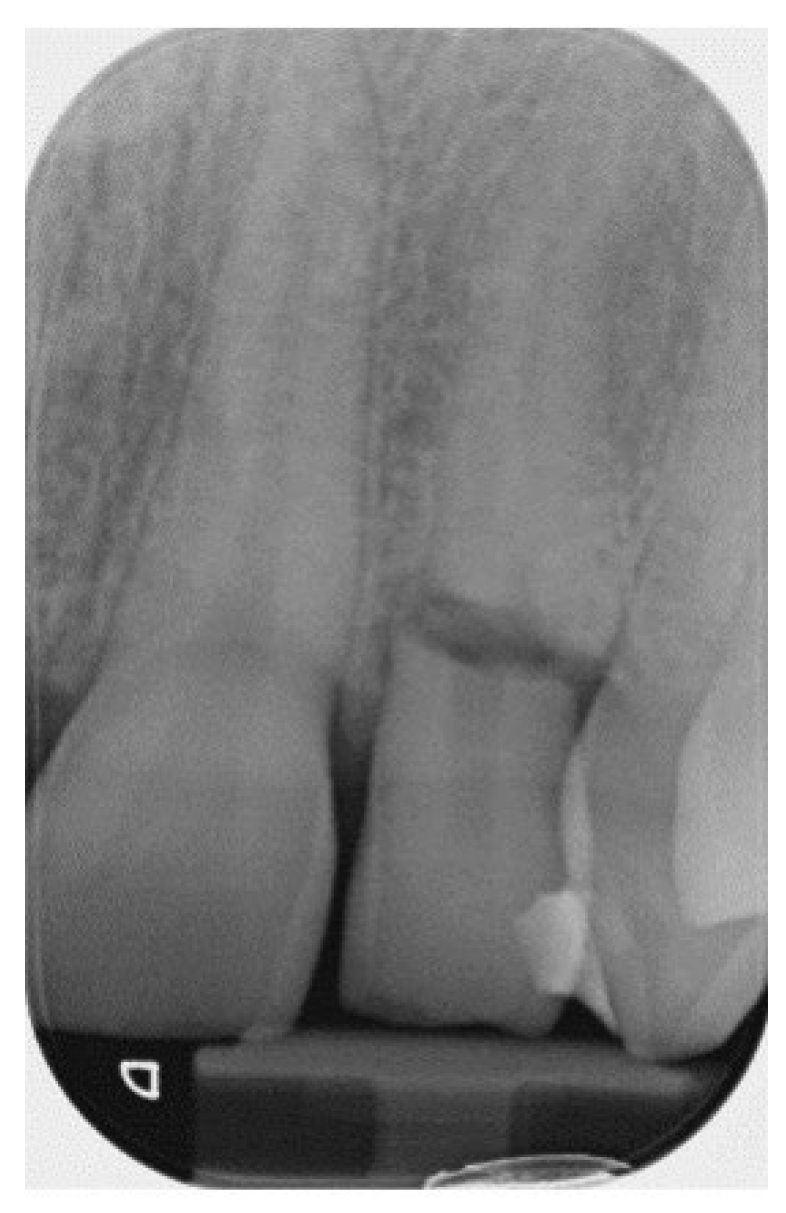

3.1. Horizontal Fractures

- A. No pulp involvement (Figure 5)